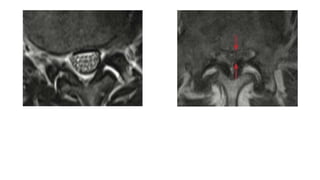

Lumbar Spinal Canal Stenosis. Sagittal (A) and axial at L3 to L4

(B) T2 weighted images. Concentric spinal canal stenosis of the

lumbar spine at multiple levels (L3 to L4 and L4 to L5) caused

by hypertrophy of the ligamenta flava, concentric disc bulging

and hypertrophic facet joint osteoarthritis.